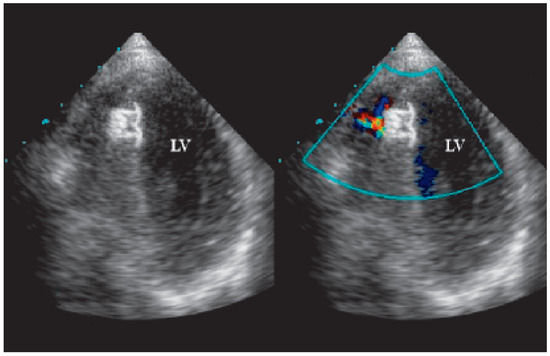

Traumatic Tamponade and Ventricular Septal Defect

A 30-year-old man sustained a knife wound in the 9th left intercostal space when he was involved in a fight as a bodyguard in a night club [...] Full article

Show Figures

Figure 1